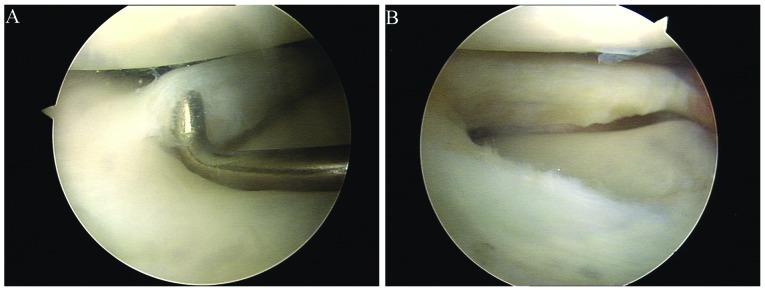

Discoid lateral meniscus of the knee causes a high morbidity in China. Since the traditional treatment to open the capsule and resect the meniscus often results in arthritis, it is now believed that a discoid lateral meniscus should be treated with arthroscopy to preserve part of the meniscus. The current study aimed to investigate the short-term clinical outcomes of arthroscopic meniscectomy for the treatment of discoid lateral meniscus tears. In the present study, we diagnosed and treated 42 patients (47 knees) with discoid lateral meniscus tears using arthroscopy between February, 2007 and December, 2010. Thirty-seven knees received partial resection of the discoid meniscus, 8 received hypo-complete resection and 2 received complete resection. Thirty-nine of the patients were followed up for a mean of 21 months (ranging from 9 to 53 months). The Lysholm scoring system was used to assess the knee function prior to surgery and during the follow-up. The results were analyzed using a Student's t-test with SPSS 12.0. Our study showed that patients with treated knees returned to normal activities within 4-6 weeks, and knee functions were more improved at 9 months after operation than 3 months, as measured by the Lysholm score (P<0.05). Arthroscopic meniscectomy is an effective treatment for discoid menisci resulting in minimal invasion, quick recovery and early functional exercise. The use of arthroscopy during surgery aids to preserve the meniscus and to reduce stress, therefore, having a beneficial effect on short-term clinical outcomes.

膝关节盘状外侧半月板在中国的发病率较高。由于传统的切开关节囊并切除半月板的治疗方法常导致关节炎,目前认为盘状外侧半月板应采用关节镜治疗以保留部分半月板。本研究旨在探讨关节镜下半月板切除术治疗盘状外侧半月板撕裂的短期临床疗效。在本研究中,我们于2007年2月至2010年12月期间,采用关节镜诊断并治疗了42例(47膝)盘状外侧半月板撕裂患者。37膝接受了盘状半月板部分切除术,8膝接受了次全切除术,2膝接受了全切除术。39例患者获得随访,平均随访时间为21个月(9至53个月)。采用Lysholm评分系统评估术前及随访期间的膝关节功能。结果采用SPSS 12.0软件进行t检验分析。我们的研究表明,接受治疗的膝关节患者在4至6周内恢复正常活动,根据Lysholm评分,术后9个月的膝关节功能改善程度高于术后3个月(P<0.05)。关节镜下半月板切除术是治疗盘状半月板的有效方法,具有创伤小、恢复快、能早期进行功能锻炼等优点。手术中使用关节镜有助于保留半月板并减轻应力,因此对短期临床疗效有有益影响。